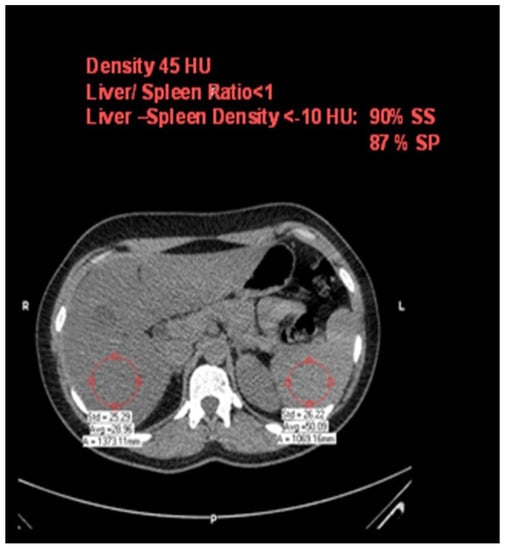

2.5. Assessment of Carotid Atherosclerosis

All patients underwent carotid ultrasounds for intima–media thickness (IMT) evaluation and plaques. A high-resolution ultrasound device (Sonos 5500; Agilent Technologies, Palo Alto, CA, USA) and a 10 MHz linear array transducer were used for carotid scans. Longitudinal views of the following were obtained: the left and right common carotids, carotid bifurcations, and internal and external carotid arteries. All ultrasound studies (carotid and brachial flow-mediated dilation) were analyzed off-line using the Prosound system by specially trained technicians who were blinded to other study variables. IMT was measured over 10 mm in the far wall of the common carotid within 2 cm proximal to the bulb (Figure 3).

Figure 3.

An ultrasound image of the carotid artery for evaluating intima–media thickness.

The thickest IMT region without focal lesions was measured. Both right and left carotids’ IMT values were averaged. The intima–media area was defined as previously described [24]:

Intima–media area in mm2 = (IMT mm) × (length over which IMT was measured in mm).

Plaques were quantified for all the carotid segments (common, internal, and external carotid arteries). Normal ranges were <7 mm for males and <0.65 for females.